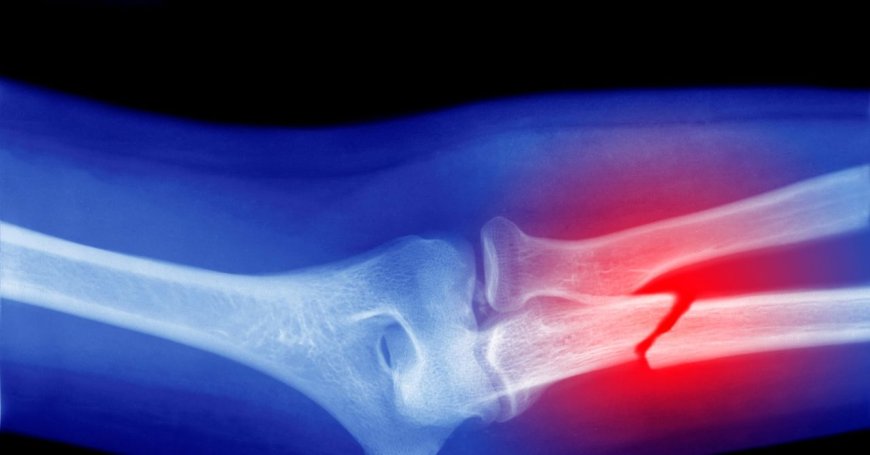

Microplastics Could Be Weakening Your Bones, Research Suggests

The review of more than 60 scientific articles showed that microplastics, among other effects, can stimulate the formation of osteoclasts, cells specialized in degrading bone tissue.